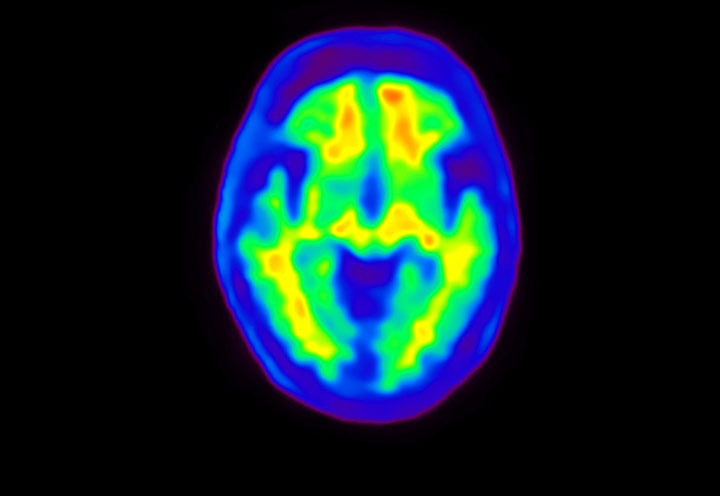

Head / Case4 : Amyloid

Axial

Courtesy : Kindai University Hospital

- Injected dose: 3.21 MBq/kg, 18F-Flutemetamol

- Uptake time: 100 minutes

- Scan time: 20 minutes